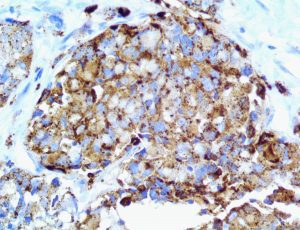

The first cytokines released are interleukin 1β (IL-1β) and tumor necrosis factor-α (TNF-α), which attract a variety of circulating white blood cells (WBCs) to the infection site, including neutrophils, monocytes, macrophages, and natural killer (NK) cells. This response, along with the antipathogenic chemicals released by these cells (i.e., complement), comprise the innate immune response. These cells directly attack the invading pathogen and also release additional cytokines, chief among them interleukin-1 and 6 (IL-6). IL-6 is essential for invoking the adaptive immune response, which calls T-cells, B-cells, and T helper (Th) cells to the infection site. IL-6 also stimulates further recruitment, proliferation and activation of macrophages.

It is the ICU physician who is most likely to witness one of the deadliest manifestations of the abnormal immunological response, the cytokine storm syndrome (CSS). This response is also referred to by some as the cytokine release syndrome (CRS). CSS is characterized by continuous activation and expansion of macrophage and lymphocyte populations, which secrete large amounts of cytokines, causing the cytokine storm. This massive cytokine release is akin to hemophagocytic lymphohistiocytosis (HLH) disease, a syndrome characterized by initial unchecked and persistent activation of cytotoxic T lymphocytes and NK cells.